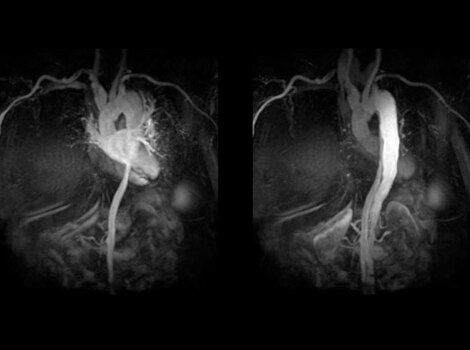

SIGNA™ Works CV Imaging & Analysis Tools

One non-invasive CMR exam to assess cardiac morphology, function, flow, tissue viability and coronary anatomy without ionizing radiation.